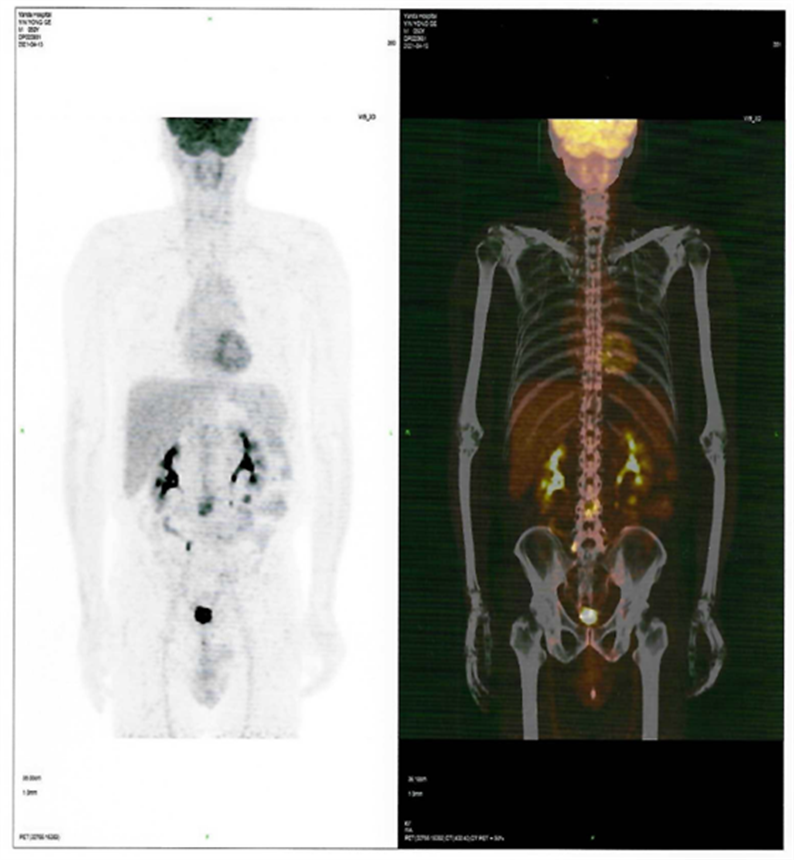

患者CAR-T 前后PET-CT檢查結果對比圖

CAR-T治療前

2021年4月12日,患者來到燕達陸道培醫(yī)院,希望借助我院的CD7 CAR –T臨床試驗項目獲得一線生機?;颊叱跞朐簳rPET-CT檢查提示:腫瘤細胞累及多處腸系膜和腹部肌肉軟組織;骨髓未累及。